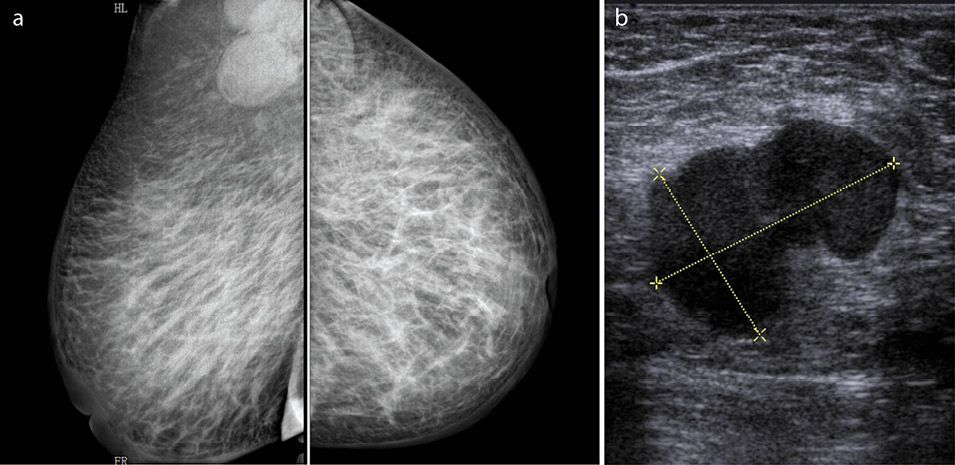

Но несмотря на возможности комплексного применения разных методов диагностики, существует ряд сложностей в визуализации отека кожи, особенно локального (рис. 4, a). Во-первых, при выраженном втяжении кожи над опухолью создается эффект утолщения кожи, но не за счет истинного отека, а за счет складки – «двойного» контура кожи (рис. 4, b). Во-вторых, после проведения биопсии на маммограммах часто определяется утолщение кожи, что затрудняет проведение дифференциальной диагностики последствий инвазивного вмешательства и опухолевого процесса (рис. 4, c). В-третьих, важными факторами диагностики, которые зачастую играют решающую роль в визуализации изменений кожи, являются высокое качество маммограмм, высокое разрешение маммографических станций, правильный алгоритм анализа полученного изображения специалистом (см. рис. 4, c).

Рис. 4: а – вторичная ОИФ, локальное – «истинное» утолщение кожи над опухолью; b – выраженное втяжение кожи над опухолью без отека; c – состояние после core-биопсии.